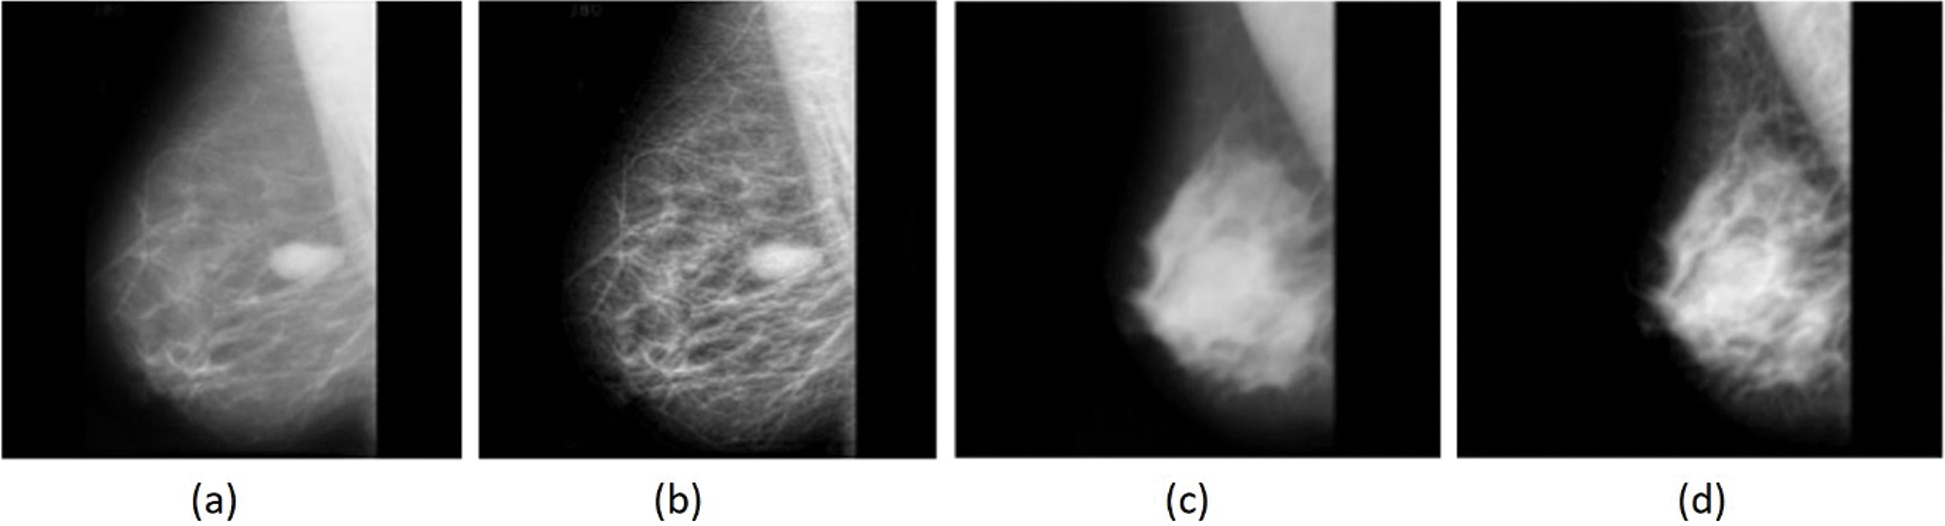

Experiments were conducted using the freely available MIAS dataset (http://www.mammoimage.org/databases/). Experimental results were analyzed using a set of performance measures consisting of sensitivity, specificity, accuracy, and F-score. Fig. 4 shows the sample original mammogram images and the preprocessed images. The figure clearly shows that the images were properly preprocessed for discarding unwanted details.

Figure 4: (a) (c) Original, (b) (d) Pre-processed images